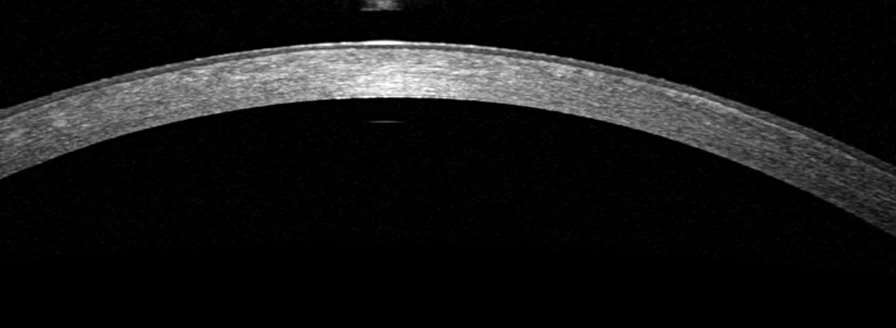

Left cornea 2 months after treatment

Use sliders to compare with pre treatment images

This girl has Granular dystrophy type 1, which is an autosomal dominant condition affecting the TGFB1 gene. She had associated recurrent erosion of the corneal epithelium. Trans epithelial PTK was performed, ablating a combined 100 microns of tissue (approximately 50 microns of epithelium and 50 microns of stroma). Two months after the procedure, the left VA was 6/9 with no pain. Ablation to a depth that eliminates all of the lesions is not recommended as this removes too much tissue. Repeat ablation would be considered in the future, should the VA fall again and eventually an anterior lamellar transplant will probably be needed.